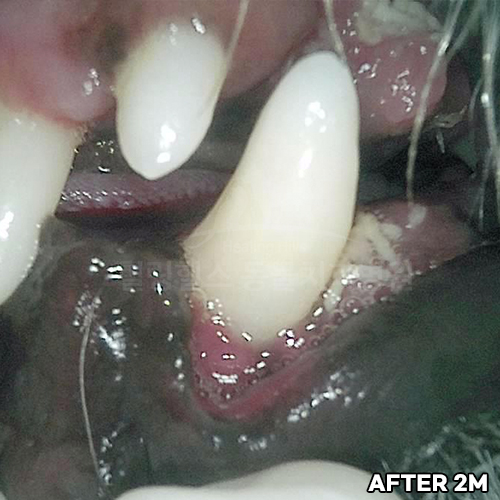

[심한 치주염 치료 후 2주 경과]